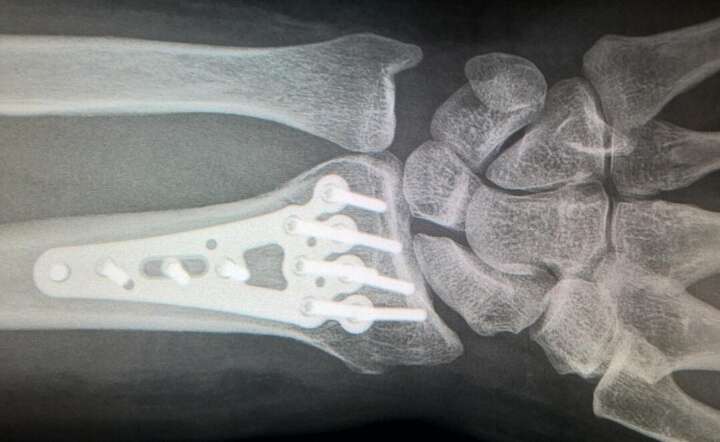

Złamane kości przedramienia na zdjęciu rentgenowskim. ZDJĘCIE ILUSTRACYJNE / autor: Pixabay

Jeśli bronimy się ręką – łamiemy nadgarstek, czasem łokieć, czasem obojczyk. Jeśli źle staniemy – cierpi staw skokowy, czasem podudzie. Przy większej energii urazu zdarzają się złamania miednicy. Różnorodność jest naprawdę ogromna.